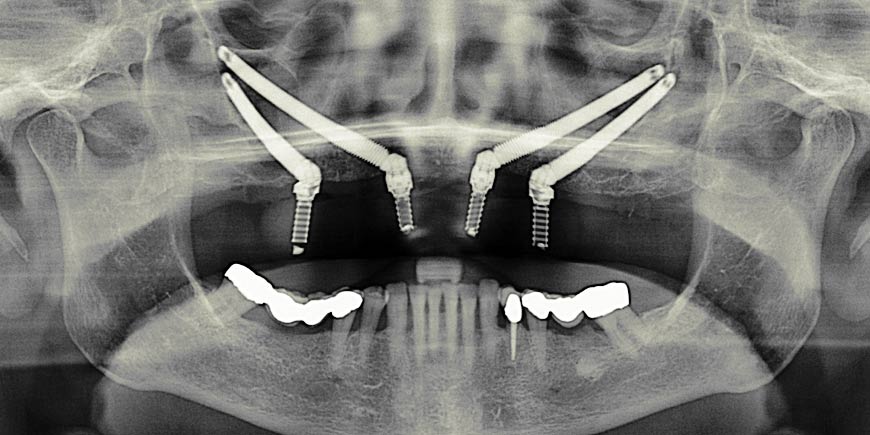

3. Zygomatic Implants

Zygomatic implants are a subtype of endosteal. They constitute another feasible alternative for patients lacking sufficient bone. This is because they are much longer than the standard endosteal and can be solidly implanted in the upper jaw bone (zygoma).